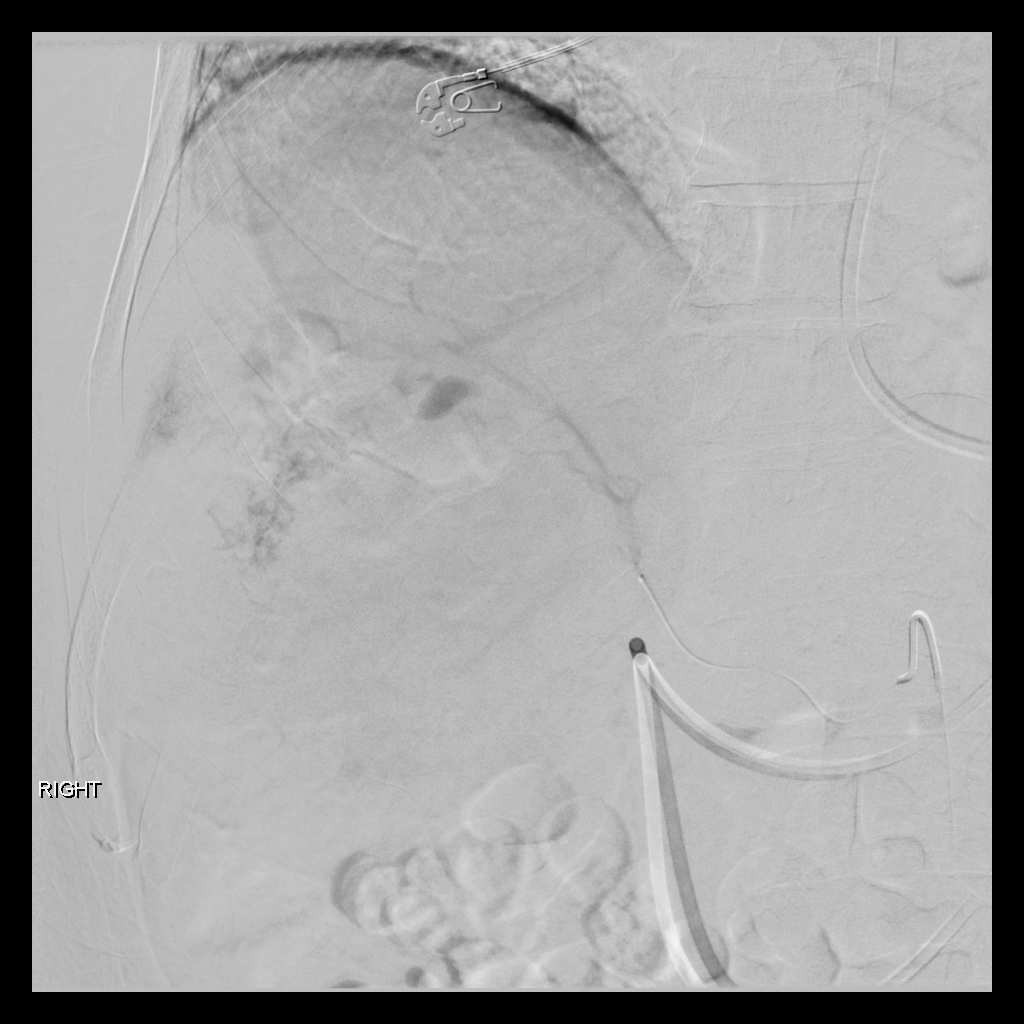

Mapping Angiogram

Comprehensive vascular mapping with CBCT to identify tumor supply and prevent extrahepatic deposition.

• Selective catherization

• Identify variant hepatic arterial anatomy

• Coil embolization of gastroduodenal or right gastric artery

• MAA injection to estimate lung shunt and dosimetry